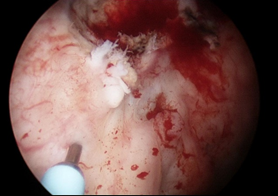

Under general anaesthetic, a rigid 20 F injection cystoscope was introduced into the bladder. Using a 23G flexible Cook Williams cystoscopic injection needle, 0.3 - 0.4ml of IH was injected into five locations at least 1cm circumferentially around the tumour bed (Figure 1). A total of 2 ml of IH tissue marker was injected into the bladder mucosa.

Figure 1 Bladder tumour clearly visible (red circle) with IH TFM injection 1cm from tumour using cystoscopic injection needle (blue arrow).